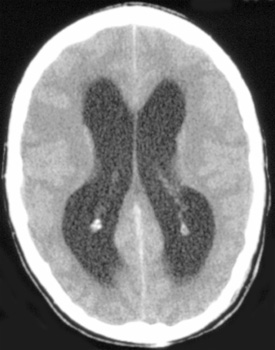

Hydrocephalus, a problem with the ratio of production of CSF to its reabsorbtion, is most frequent in children. Communicating hydrocephalus is the most common and is due to arachnoid villi and subarachnoid space obstruction. Obstructive hydrocephalus is less common but may occur as a result of the following:

![]() ![]() ![]() In these sections from the same patient notice the enlagement of the ventricles and cisterns that occurs with hydrocephalus. |